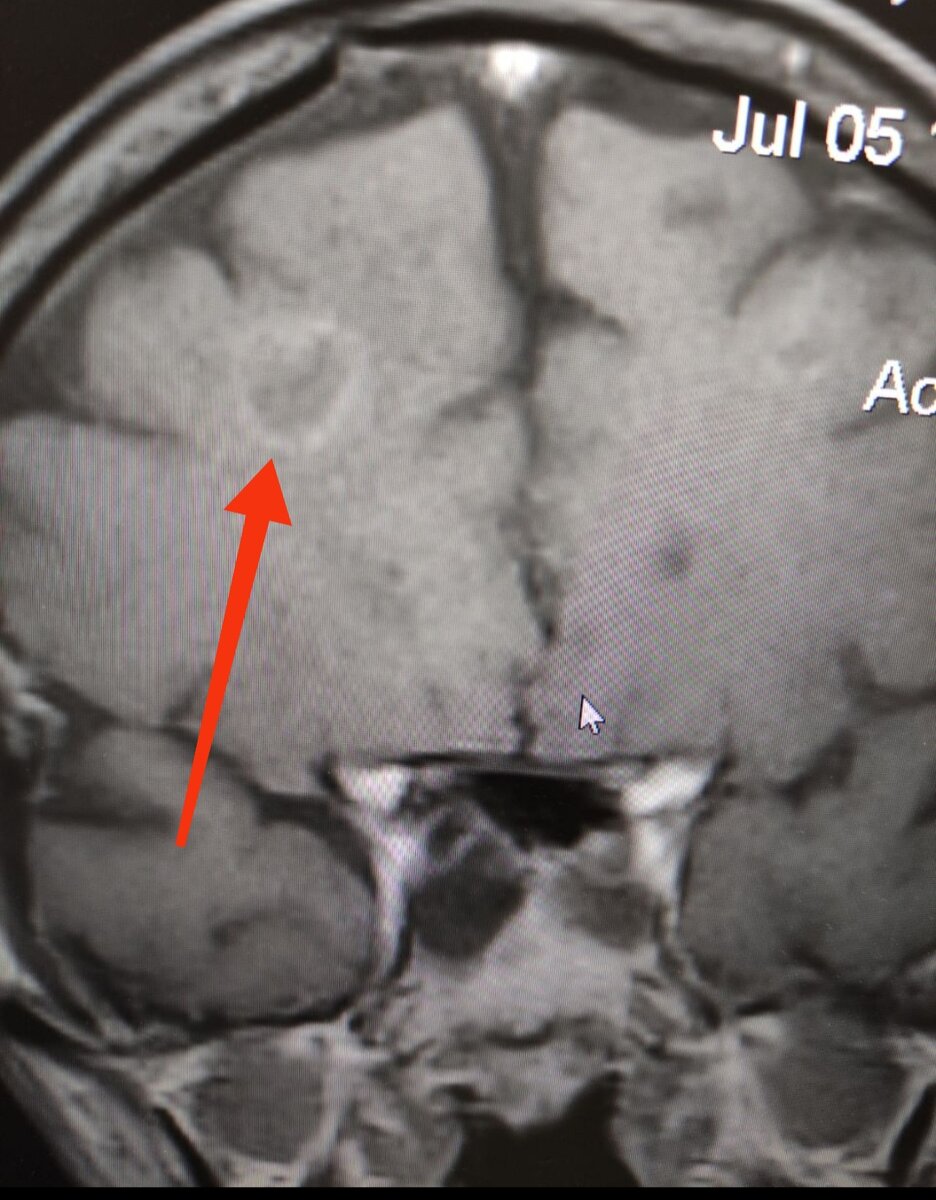

Недавно пациенту МРТ головного мозга с контрастированием и увидели причину того, что было расценено как инсульт.

МРТ головного мозга с контрастированием

Выше- МРТ головного мозга с округлым образованием, накапливающим контрастное вещество по периферии. Это и есть токсоплазмозная киста и их обычно несколько.